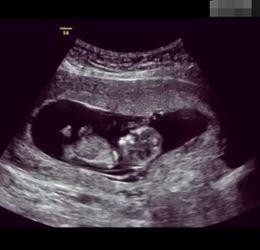

B超,全称超声波检查,是一种无创的医学检查方法。通过B超,医生可以观察到胎儿在母体内的生长情况,包括胎心、胎动、羊水等。而B超视频,则是将这一过程以动态的形式呈现出来,让准妈妈和准爸爸们能够亲眼见证宝宝的成长。

1. 胚胎阶段:在这个阶段,宝宝还只是一个小小的胚胎,但B超视频已经能够清晰地看到他的心跳和轮廓了。这个时候的宝宝,就像是一个小小的探险家,在妈妈的肚子里探索着这个未知的世界。

2. 胎儿阶段:随着宝宝的成长,B超视频中的画面也越来越丰富。这个时候,我们可以看到宝宝的小手、小脚,甚至还能看到他吞咽羊水的样子。这个时候的宝宝,已经能够感受到妈妈的爱了。